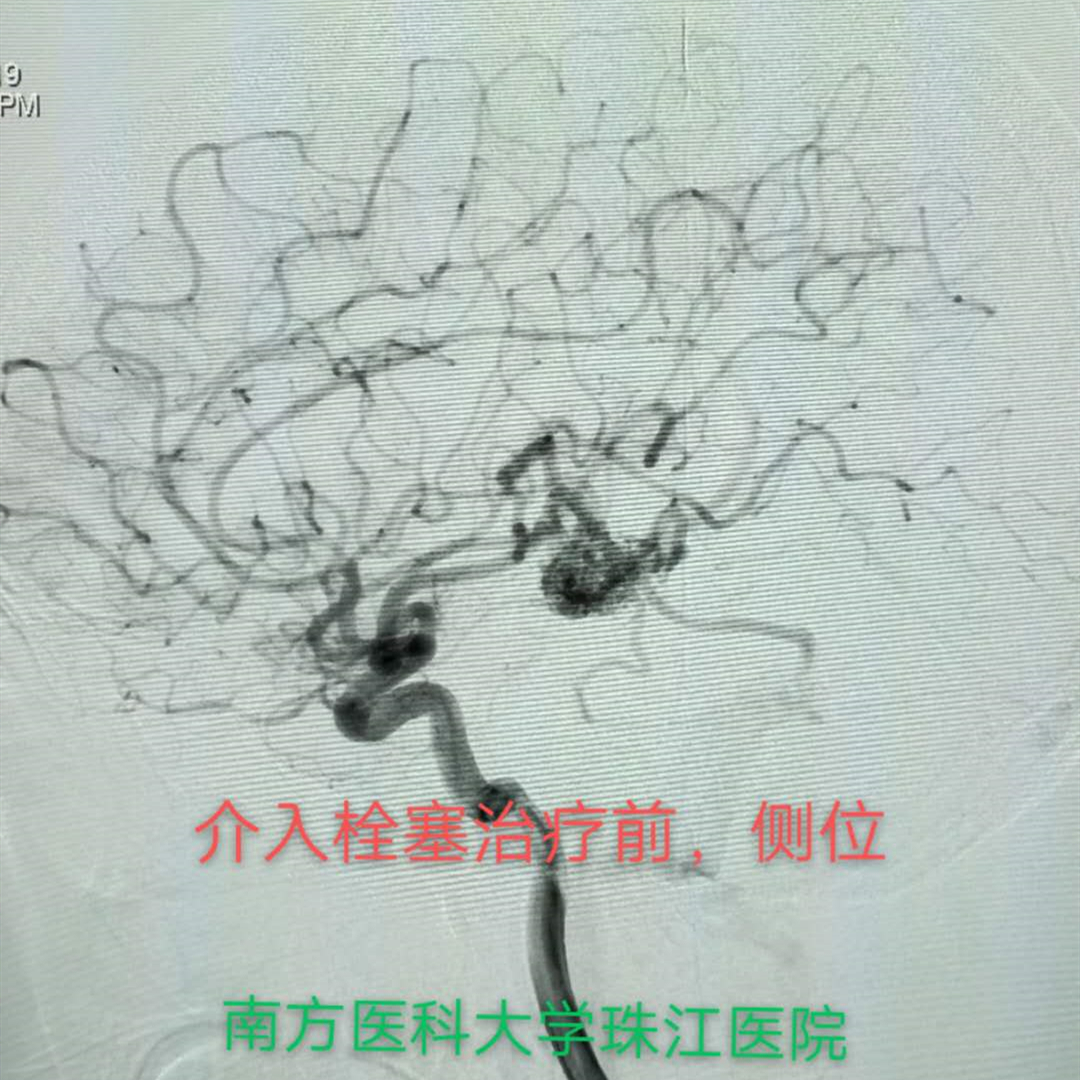

血管内栓塞治疗

主要是采用医用胶填充病灶并闭塞滋养血管,同时保留侧支血管到正常的邻近脑组织。是目前治疗动静脉畸形的主要方法。

病例1 动脉入路

大多数情况下,通过介入治疗可以达到完全治愈的目的,针对部分患者血管内栓塞治疗是手术切除或放射外科治疗前的有效辅助治疗办法,通过一次或数次栓塞治疗将畸形团变小、栓塞其中的伴发动脉瘤、高流量动静脉瘘等,为手术、放射外科治疗创造条件。